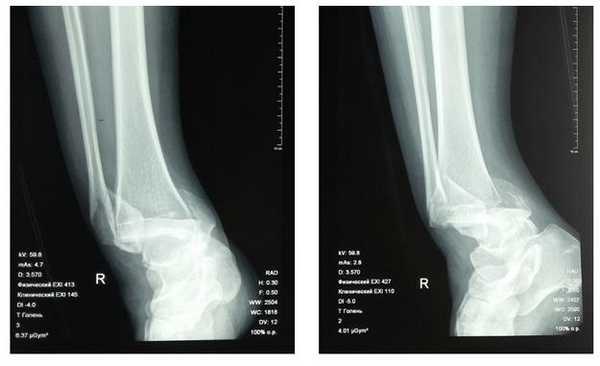

Клинический случай 2. Перелом обеих лодыжек с вывихом стопы кнаружи, кзади.

Пациентка Л. 50 лет, травма в быту, получила закрытый перелом обеих лодыжек с вывихом стопы кнаружи и кзади. Данный случай интересен значительным повреждением мягких тканей произошедшем при травме и потребовавшем значительных усилий в борьбе с отёком, а также морфологией перелома внутренней лодыжки, сломавшейся одним большим блоком вместе с задним краев большеберцовой кости, что потребовало её фиксации при помощи пластины и винтов.

В связи с выраженным отёком мягких тканей, высоким риском некроза краёв ран и инфекционных осложнений пациентке с целью предоперационной подготовки выполнялись скелетное вытяжение, сосудистая и метаболическая терапия, лимфодренаж, физиотерапия. После спадения отёка, на 3 день после поступления выполнено оперативное вмешательство: открытая репозиция, остеосинтез переломов наружной и внутренней лодыжек пластинами и винтами.

Через 4 дня пациентка выписана на амбулаторное долечивание. Послеоперационные раны зажили первичным натяжением, швы удалены через 14 дней.

Через 6 недель после первичного вмешательства произведено удаление позиционного винта, пациентка приступила к активной разработке движений в голеностопном суставе.

Амплитуда движений через 8 недель после травмы и оперативного вмешательства по поводу этого тяжёлого повреждения близка к полной. Пациентка ходит с полной опорой, не используя костыли или трость, не хромает, боли не беспокоят. Сохраняется умеренный отёк в области голеностопного сустава.